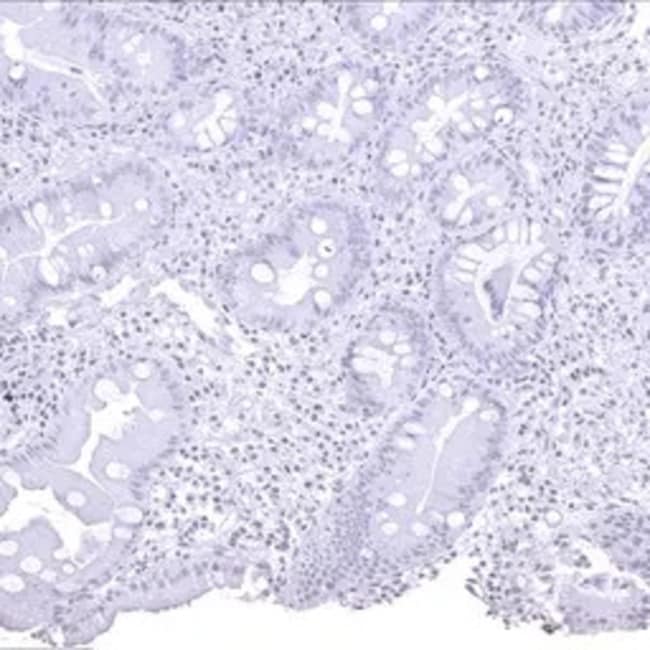

The Helicobacter pylori Catalase antibody [MSVA-466M] HistoMAX™ (GTX04479) is a Mouse Monoclonal antibody in the GeneTex HistoMAX portfolio. The antibody is extensively evaluated for IHC-P using formalin-fixed human normal tissues (more than 70 different sections) and cancer tissue arrays to guarantee specificity and best-in-class performance. Information regarding both manual and autostainer staining protocols are available.Figure Legend: IHC-P analysis of human stomach tissue using GTX04479 Helicobacter pylori Catalase antibody [MSVA-466M] HistoMAX. Complete absence of helicobacter pylori in a stomach biopsy.